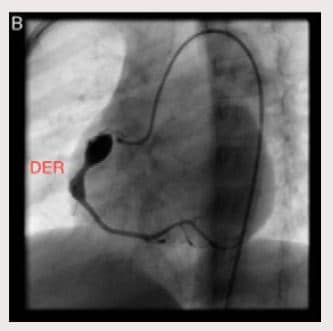

En control ecocardiográfico al mes aún persistían los aneurismas de igual tamaño. Dos meses luego del egreso, presentó fiebre de 39-40? durante dos días, consultó a Urgencias y se administró benzetacil por diagnóstico de amigdalitis. Se hospitalizó para estudio y presentó hipercolesterolemia, trombocitosis y pruebas de función hepática alteradas. El ecocardiograma evidenció aneurisma sacular gigante del tronco coronario izquierdo (13 mm) y dos aneurismas de tamaño moderado a grande (8,2 mm la proximal y 6,6 mm la distal) en la coronaria derecha (Fig. 1A y B). Se inició tratamiento con heparina durante dos meses y posteriormente se trató con warfarina 0,1 mg/kg/día y ácido acetil salicílico 50 mg/día. Se dio de alta con fórmula de ácido acetil-salicílico. Ante la persistencia de aneurismas gigantes se remitió para valoración por Hemodinámica, quienes ordenaron cateterismo cardiaco (Figs. 2A, 2B, 3A y 3B). Se trató con heparina de bajo peso molecular durante un mes y luego con Warfarina en forma permanente.

Figura 2 B. Diagrama de cateterismo cardíaco con tres aneurismas coronarios (dos en la arteria coronaria derecha-ACD y uno en la arteria izquierda

– ACI).

Figura 3 B. Cateterismo cardíaco en el que observan dos aneurismas en la arteria coronaria derecha (uno proximal de mayor tamaño y uno distal, de menor tamaño).